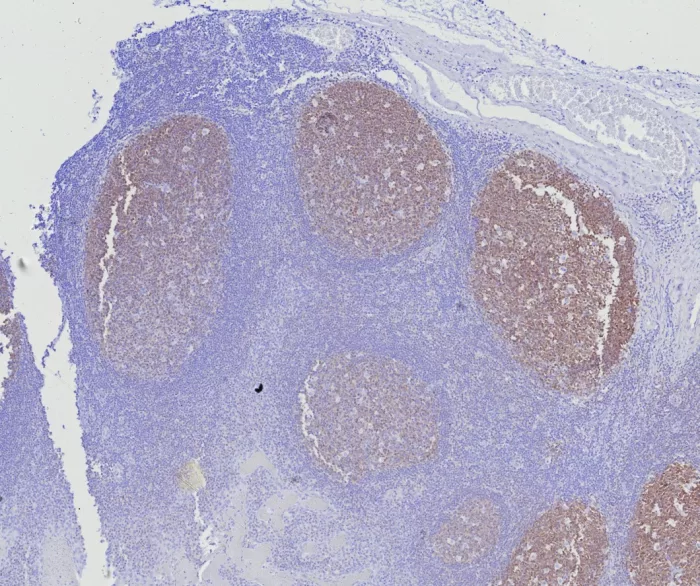

Formalin-fixed, paraffin-embedded human tonsil stained with BOB1 Mouse Monoclonal Antibody (BOB1/7469). HIER: Tris/EDTA, pH9.0, 45min. 2°C: HRP-polymer, 30min. DAB, 5min.

BOB.1 expression in a variety of established B-cell lines, representing different stages of B-cell development, has suggested a constitutive, B-cell-specific expression pattern. LP cells in nodular lymphocyte predominant Hodgkin lymphoma, because they are germinal center-derived, are consistently immuno-positive for BOB.1. Conversely, only some cases of classical Hodgkin lymphoma show BOB.1 immuno-reactivity within the Hodgkin and Reed-Sternberg cells. �Expression of BOB.1 has been reported in follicular center cell lymphoma, diffuse large B-cell lymphoma and some cases of acute myeloid leukemia. �B-CLL, marginal zone lymphoma, and mantle cell lymphoma may show weak to moderate immunoreactivity.